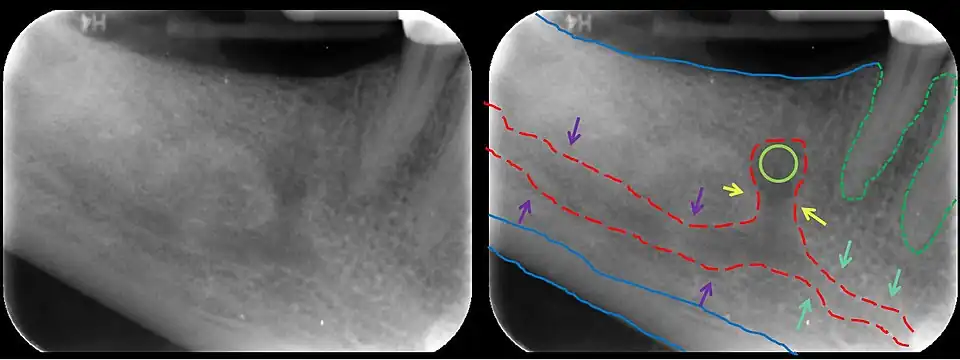

The mandibular incisive canal (indicated here by coral green arrows) continuing anteriorly (to the right) from the mandibular canal (purple arrows) after the mental foramen (light green circle)

In human anatomy, the mandibular canal is a canal within the mandible that contains the inferior alveolar nerve, inferior alveolar artery, and inferior alveolar vein. It runs obliquely downward and forward in the ramus, and then horizontally forward in the body, where it is placed under the alveoli and communicates with them by small openings.

On arriving at the incisor teeth, it turns back to communicate with the mental foramen, giving off a small canal known as the mandibular incisive canal, which run to the cavities containing the incisor teeth.[1] It carries branches of the inferior alveolar nerve and artery.

The mandibular canal is continuous with two foramina: the mental foramen which opens in the mental region of the mandible and carried the distal fibres of the inferior alveolar nerve as the mental nerve; and the mandibular foramen on medial aspect of ramus, into which the mandibular nerve enters to become the inferior alveolar nerve. The mandibular canal often runs close to the apices of the third molar tooth, and the inferior alveolar nerve can become damaged during removal of this tooth, causing sensory disturbance in the distribution of the nerve. This is sometimes the case for the second or first molar teeth, and care must be taken during removal or root canal treatment in such cases to prevent nerve injury or extrusion of root canal filling materials.[2]